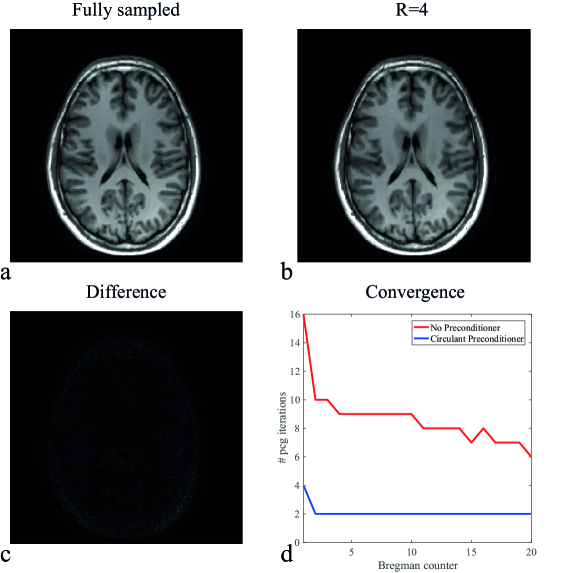

The method also works for different coil configurations. In Fig. 8 the result is shown when using the 15-channel head coil for a brain scan. The circulant preconditioner clearly reduces the number of iterations, with an overall speed-up factor of 4.1 in the PCG part.